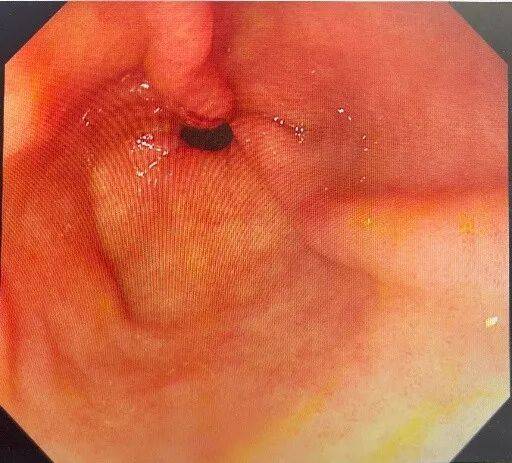

明确诊断后予抑酸、溶石、补液等对症处理,2周复查胃镜提示:胃多发溃疡(H1期)。胃底、胃体黏膜光光滑,胃石已溶解消除。